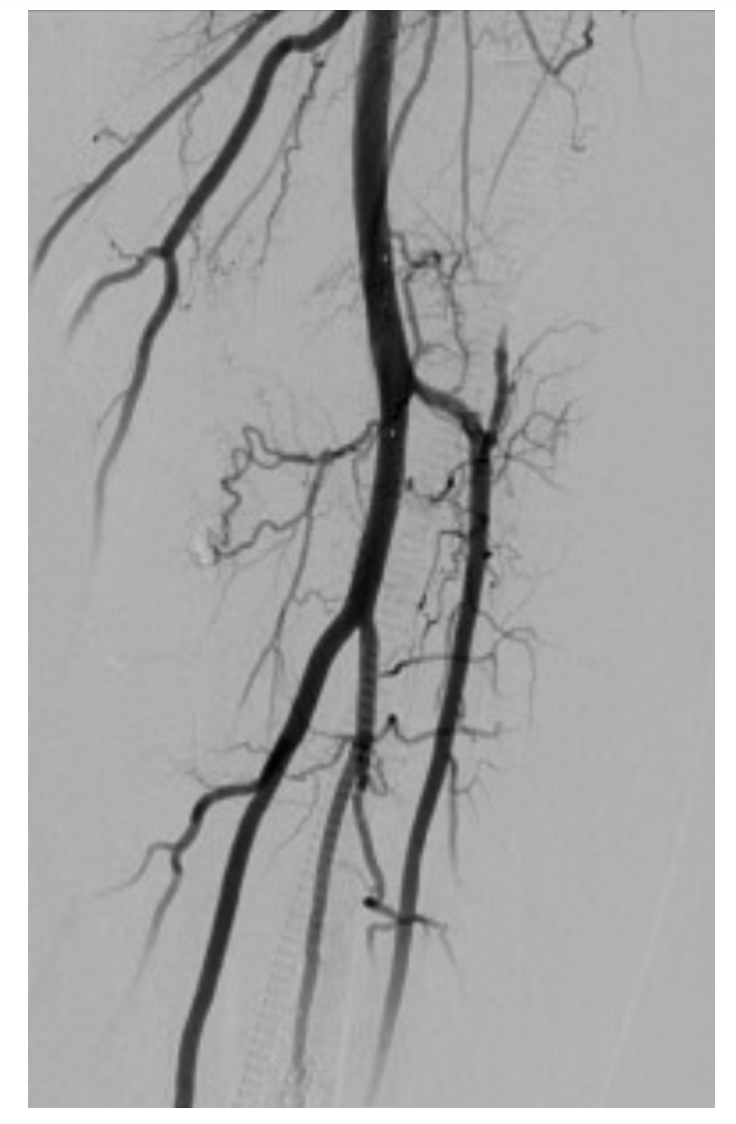

A 6F 70 cm sheath was advanced to the proximal left popliteal artery via contralateral femoral access. An .014-inch Luge wire (Boston Scientific) with support of a 1.2 mm over-the-wire Mini Trek balloon (Abbott Vascular) was advanced through the dissection plane into the left anterior tibial artery. Distal injection confirmed intraluminal crossing. The balloon was removed, a SpiderFX (Medtronic) distal protection device was placed in the distal popliteal artery and optical coherence tomography (OCT) (Abbott Vascular) imaging was performed (Figure 4A-C). OCT images demonstrated an intimal tear of the left popliteal artery and very mild atherosclerotic disease. A 6 x 40 mm Chocolate balloon (Medtronic) was advanced to the site of the dissection and the lesion was dilated to 4 atmospheres (atm) for 3 minutes. Post PTA angiographic images showed TIMI-3 flow without evidence of dissection, perforation, or embolization (Figure 5). To our knowledge, there are no reported cases or series using OCT to confirm popliteal artery dissection.

Anatomically, the popliteal artery is a relatively short vascular segment subjected to movement and potent external forces, including compression, torsion, elongation, and flexion.2 The patient in this case report had no known comorbidities associated with spontaneous arterial dissections. In the absence of significant focal atherosclerosis as demonstrated by OCT, one could hypothesize that focal dissection was the result of a transient increase in popliteal blood pressure due to prolonged sitting, which in turn caused elevation of the intima and a significant reduction in the diameter of the vessel true lumen, providing the mechanism for distal critical limb ischemia. Figures 4A-C illustrate the presence of a dissection flap, no significant atherosclerotic burden, and a false lumen pouch with residual thrombus. The blind sub-intimal pouch with stasis of flow leads to thrombus formation, expansion of the false lumen, and compression of the true lumen. We can’t comment on the presence of micro-fenestrations along the dissection flap, since the crossing of the dissection flap with the wire and support catheter immediately improved antegrade flow. Similar OCT images and observations have been recently described by Jackson et al in 65 patients with spontaneous coronary dissection.3